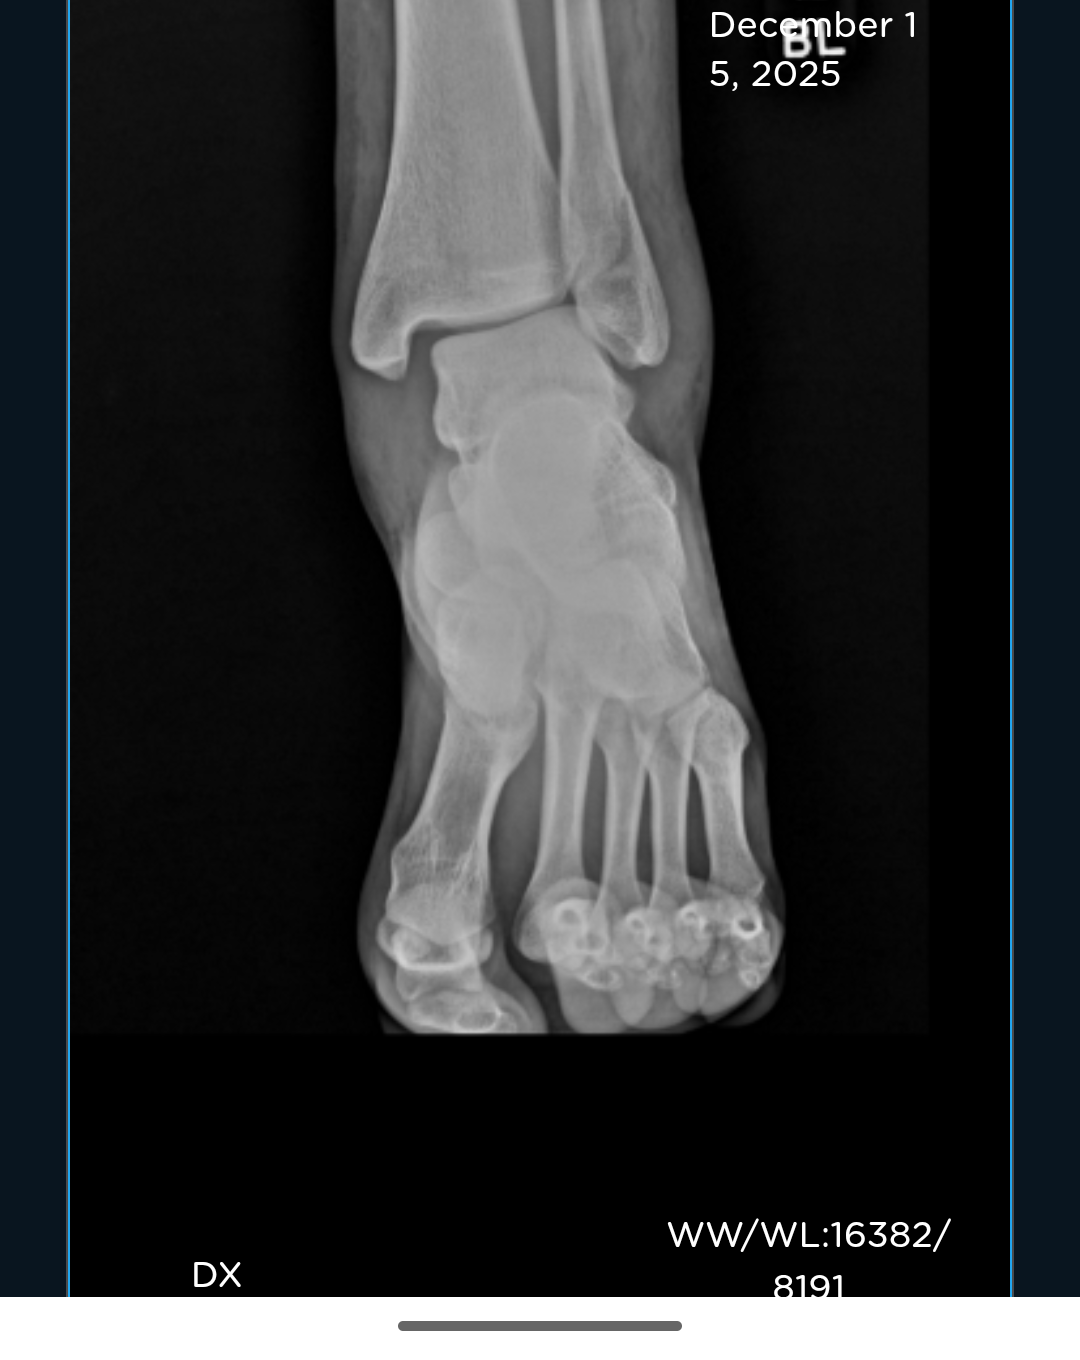

Due to the nature of my injury, a spiral fracture in my fibula and a displaced tibia, I now need surgery on it immediately. Without insurance, my out of pocket cost will be $10-13k on top of what I've already had to pay out of pocket just to get looked at and told to go elsewhere. At this time, I am unable to pay the amount required for the surgery. As I'm uninsured, currently not working and won't be able to for quite some time while I'm recovering, I'm hoping to see if I can somehow manage to come up with the money and so here I am.